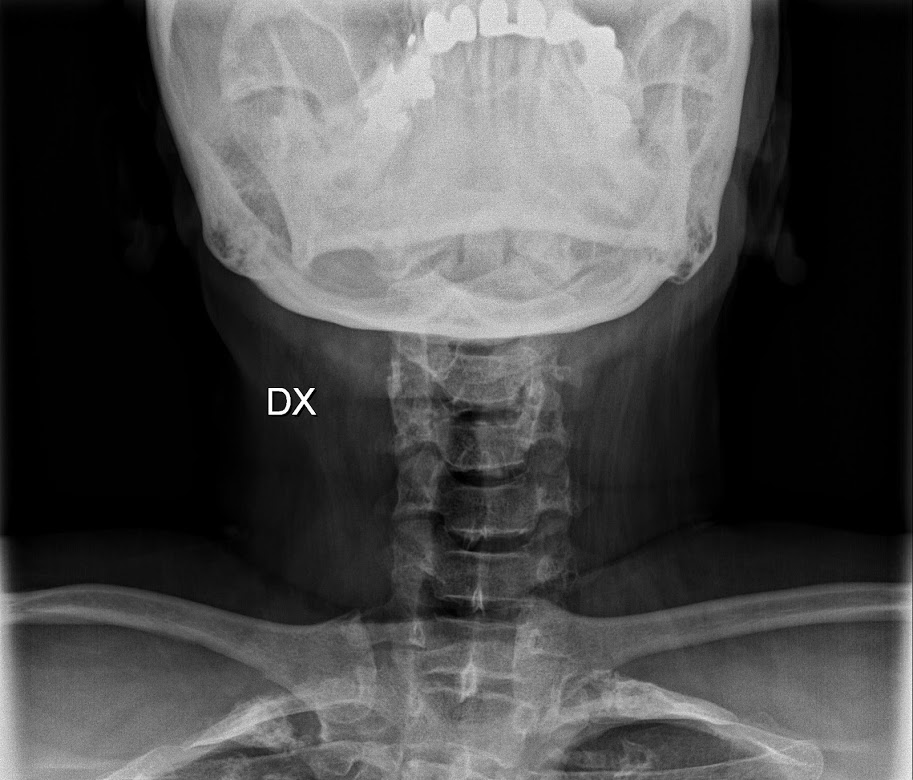

Le anomalie della colonna vertebrale sono frequenti nelle persone con pseudoacondroplasia e possono manifestarsi in diverse forme, contribuendo a dolore, rigidità e limitazioni funzionali.

Tra le principali alterazioni si osservano:

scoliosi, ovvero una curvatura laterale della colonna vertebrale a forma di “S”;

• iperlordosi lombare, caratterizzata da una curvatura eccessiva verso l’interno del tratto lombare;

• cifosi, una curvatura anomala della parte superiore della colonna vertebrale che provoca un arrotondamento accentuato della schiena.

Queste deformità possono peggiorare nel tempo e richiedono un attento monitoraggio clinico, oltre a interventi terapeutici e riabilitativi mirati.

Le complicanze della mia condizione si sono estese negli anni a dolori cronici articolari e cervicali, glaucoma, allergie plasmaclergiche e apnee notturne, risolte grazie all’uso della CPAP. Non posso assumere antinfiammatori derivati dall’aspirina, quindi convivo con il dolore in tutta la sua intensità. Questa esperienza personale mostra quanto la pseudoacondroplasia possa variare in gravità e sottolinea l’importanza di un approccio multidisciplinare e personalizzato, oltre alla necessità di una maggiore attenzione scientifica verso forme rare e uniche